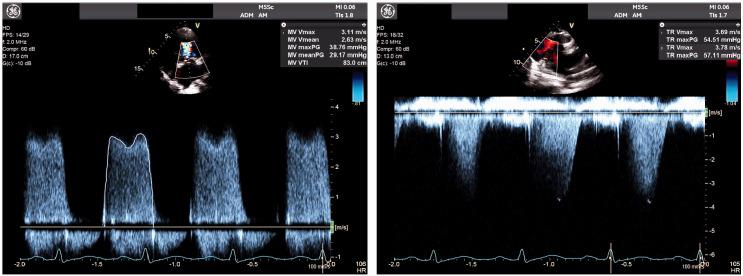

A 28-year-old aboriginal woman with known severe MS was found to be pregnant during routine health review, despite contraceptive efforts. Echocardiography demonstrated mean mitral valve (MV) gradient 14 mmHg; stress echocardiography demonstrated increased MV gradient 28-32 mmHg at peak exercise and post-exercise pulmonary artery pressure 56 + 3 mmHg with marked dynamic D-shaped septal flattening. Left ventricular systolic function remained preserved. She remained remarkably asymptomatic and underwent successful elective induction of labour at 34 weeks. Postpartum, she remained euvolaemic despite worsening MV gradients and new atrial fibrillation (AF). She subsequently underwent balloon mitral valvuloplasty with good result.

一名28岁患有严重MS的原住民女性在常规健康检查中被发现怀孕,尽管采取了避孕措施。超声心动图显示二尖瓣(MV)平均梯度为14 mmHg;负荷超声心动图显示运动峰值时MV梯度增加至28 - 32 mmHg,运动后肺动脉压为56 + 3 mmHg,伴有明显的动态D形室间隔扁平。左心室收缩功能保持正常。她一直没有明显症状,并在34周时成功进行了择期引产。产后,尽管MV梯度恶化且出现新的心房颤动(AF),但她仍保持血容量正常。随后她接受了球囊二尖瓣成形术,效果良好。